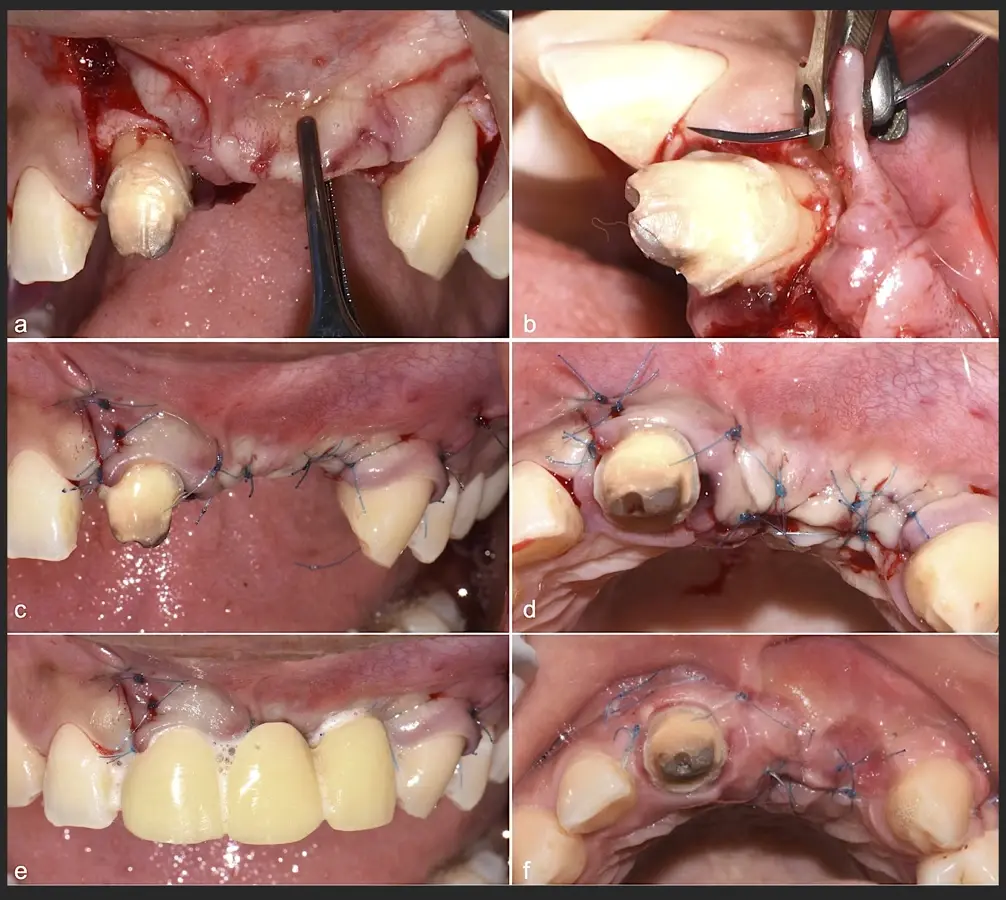

Paciente de sexo femenino de 36 años de edad, llega a la consulta por presentar una restauración protésica inadecuada. En el examen clínico se observa una restauración protésica provisional acrílica sobre las piezas 1.1 y 2.2. Adicionalmente, se aprecia recesión gingival a nivel de la pieza 2.2 y deficiencia horizontal severa de reborde a nivel de la zona edéntula correspondiente a la pieza 2.1. En la evaluación tomográfica se observa ausencia total de tabla ósea vestibular en la pieza 2.2, y se corrobora el déficit en la zona edéntula de la pieza 2.1, para lo cual se indica una reconstrucción de estructuras óseas con hueso en bloque de origen bovino y posteriormente la colocación de implantes dentales.

Figura 45. Afrontamiento de colgajo y sutura (a - e). Control a los 7 días postquirúrgico (f).